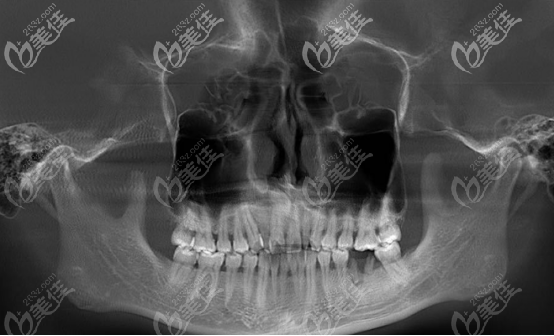

(X片的檢查結(jié)果)

檢查后的10個問題:

1、安氏I類(上頜的恒磨牙咬住下頜恒磨牙,其他牙齒咬合均異常)

2、骨性III類(俗稱的地包天)

3、牙弓尖圓形(牙弓的整個輪廓呈現(xiàn)前尖后圓型,正常是橢圓形)

4、上下頜前牙中度擁擠

5、過小牙(錐形牙,牙齒發(fā)育不全)

6、前牙區(qū)對刃(就是前牙的咬合無法覆蓋)

7、牙齒反頜(就是下牙咬在了上牙的外面)

8、殘根(齲壞將牙齒腐蝕后剩下的部分)

9、埋伏多生牙(多長出來的牙齒,埋伏在牙槽骨里面很深的位置)

10、上下中線均右偏(牙齒歪斜)